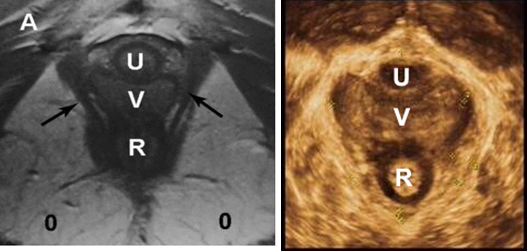

MRI图与正常盆底三维图像

肛门括约肌完整(左图)

产后10年,肛门括约肌损伤(右图)